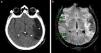

El hallazgo más frecuente quizás lo constituya la presencia de pequeñas imágenes focales que se distribuyen en la sustancia blanca encefálica y se visualizan hiperintensas en la RM ponderada en T2 o FLAIR (fig. 1). Estas imágenes se observan en aproximadamente un 12-47% de los pacientes migrañosos, siendo incierto su origen y significado clínico3. La importancia de este hallazgo radica en la posible confusión que puede generar con otras etiologías, como la esclerosis múltiple y los fenómenos microangiopáticos.

Si bien existen otros cambios estructurales asociados a la migraña, la complicación más importante de esta patología tal vez sea el infarto migrañoso3. En estos casos, los pacientes suelen presentar intensas crisis migrañosas acompañadas de otros síntomas, como aura y déficit neurológico focal, habitualmente sin secuela funcional. Es común en mujeres migrañosas menores de 45 años y con factores de riesgo cardiovascular. En imágenes, el área afectada muestra una pequeña lesión, generalmente menor de 3cm, con características de infarto, muchas veces silente (fig. 2).